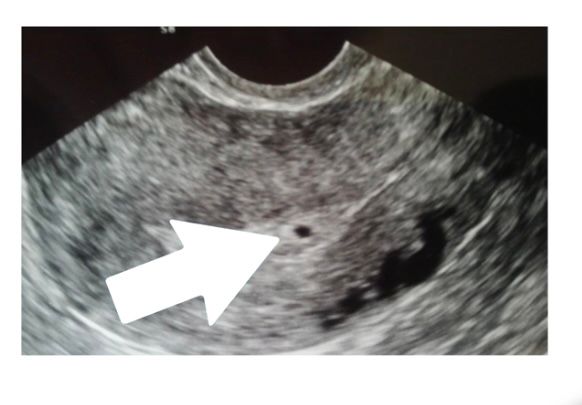

У меня срок 5-6 недель. На УЗИ овальная полость чёрная и внутри светлым контуром шарит -ПЯ.

Свет в окошке, вот так Изображение

Какая же это киста, это ваш малыш уже) потерпите все хорошо будет, ещё рановато для узи

Анастасия, это просто не мое фото,но идентично тому что я видела.. я не хотела так рано,это врач так решила. Благодарю за ответ